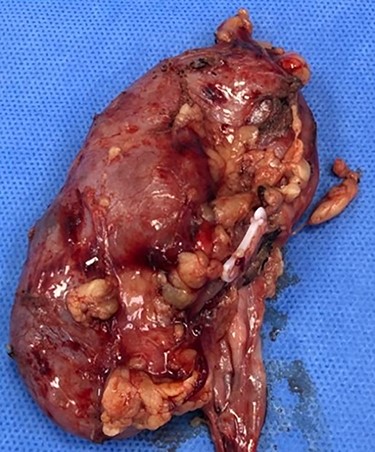

Consequently, the patient was scheduled for Rt radical nephrectomy which was done through Rt transverse paramedian incision. The renal specimen is shown in Fig. 5. The postoperative course went smoothly except for the wound infection which was managed conservatively. Histopathological examination showed that it was clear cell renal carcinoma, grade 2, T3a, free renal vein and lymph nodes were also free from any metastatic deposits (Score0/8; Fig. 6).

H&E microscopic appearance of clear cell renal carcinoma (100 times magnification).